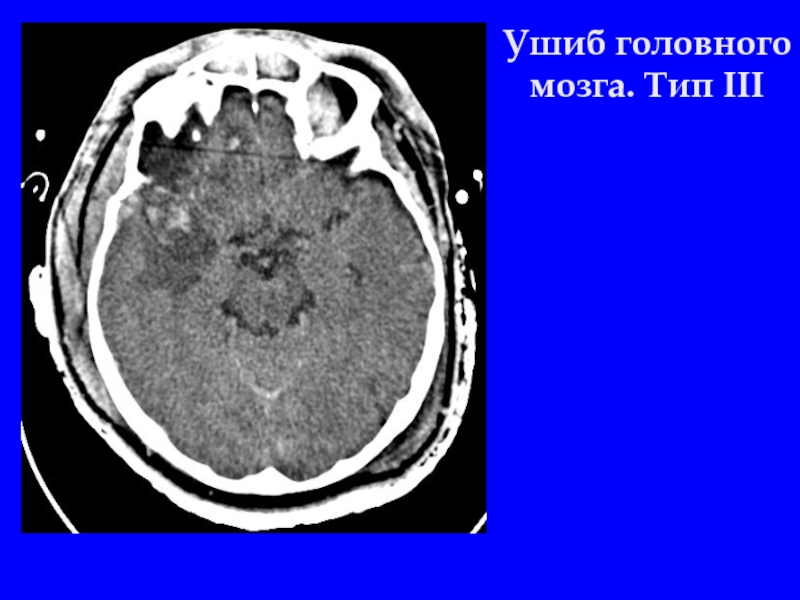

Слайд 5Ушиб головного мозга. Тип III